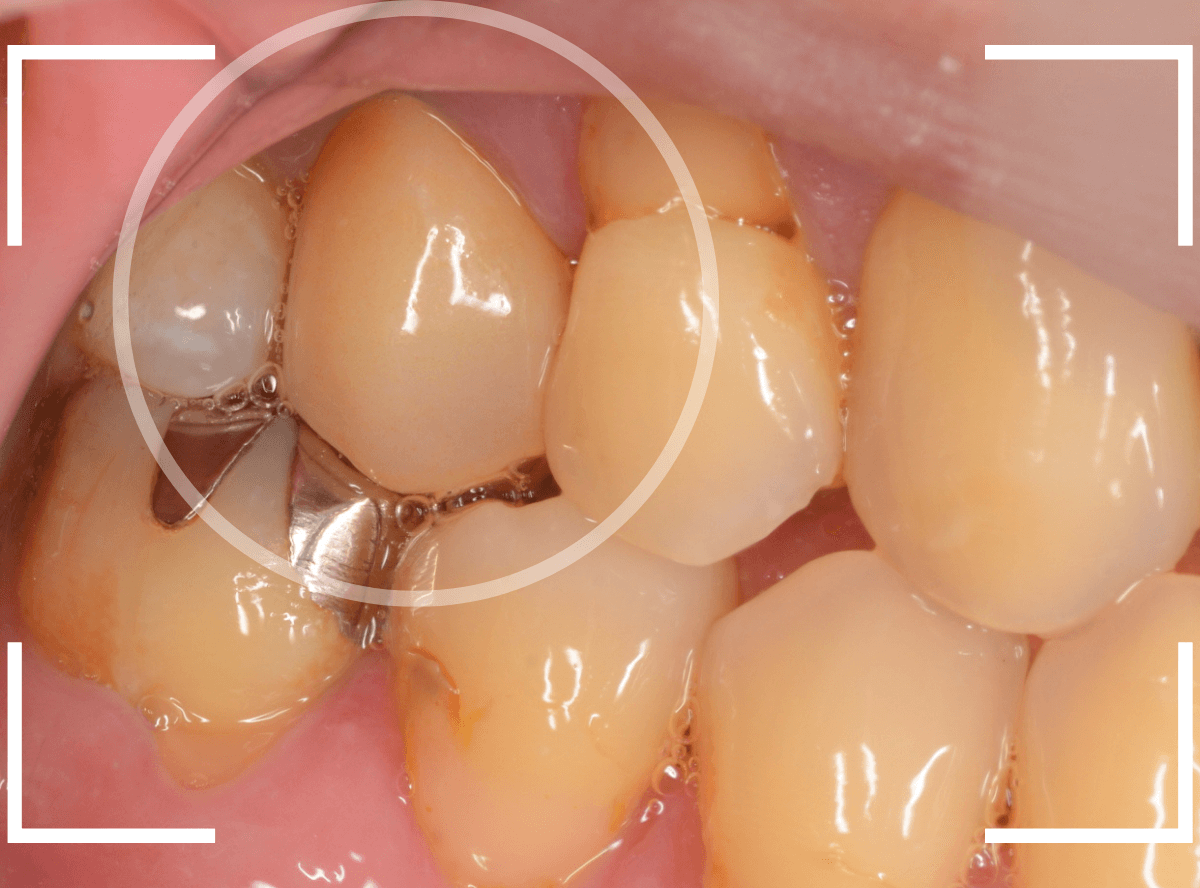

「さし歯が割れた」という訴えで来院された方のケースです。

さし歯が真っ二つに割れています。

お話を聞くと少し前に保険治療で修復したさし歯だそうで、おそらくCADCAM冠だと思われます。

CADCAM冠は、保険適応で製作できる白いさし歯ですが、金属冠やジルコニアなどに比べて脆弱で、今回にように、短期間で破折するケースも多いため、当院では取り扱っておりません。

「今回は、しっかりしたもので治療したい」という患者さんの要望により、オールジルコニア・クラウンでの製作となりました。

さし歯を外して、色合わせ・型取りをします。